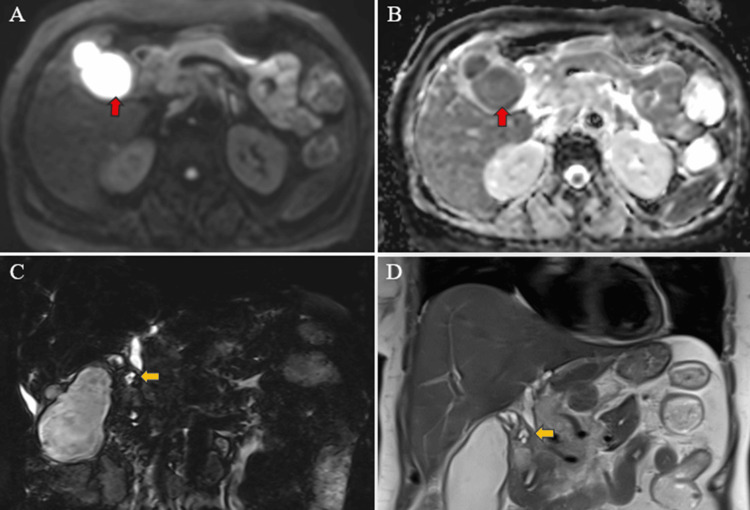

Magnetic resonance (MR) abdomen imaging with MR cholangiopancreatography (MRCP) revealed an overdistended gallbladder with circumferential wall thickening measuring 4 mm. Bile appeared hypointense on T2-weighted imaging (T2WI), indicative of sludge or thick material, with diffusion restriction on diffusion-weighted imaging (DWI) and low apparent diffusion coefficient (ADC) values. A 7 mm defect was noted in the body region, with T2 hyperintense pericholecystic fluid collection demonstrating diffusion restriction adjacent to the body. Mild dilatation of the IHBR was observed in both the right and left lobes. The CBD measured 8 mm in diameter, with narrowing of the mid-CBD due to circumferential wall thickening measuring 4 mm. The remainder of the CBD appeared normal in caliber (Figures 9–10).

Multiple enlarged lymph nodes were noted at various locations, including the porta hepatis, peripancreatic region adjacent to the pancreatic head, celiac region, aorto-caval region, pre-aortic, left para-aortic region, and retrocaval region (Figure 11). These lymph nodes exhibited T1WI hypointensity and T2WI heterogeneous hyperintensity, with central necrotic areas of variable sizes. Some lymph nodes demonstrated diffusion restriction on DWI and appeared coalescent. The pancreas appeared normal. Visualized lower lobes of both lungs exhibited well-defined T2WI hyperintense lesions ranging in size from 2 to 15 mm, with peripheral and subpleural distribution.

These findings were suggestive of a stricture in the mid-CBD, likely neoplastic (cholangiocarcinoma), resulting in proximal biliary obstructive dilatation. Additionally, the gallbladder exhibited changes consistent with empyema and contained perforation. Multiple metastatic lymph nodes were observed in the retroperitoneum and porta hepatis, along with multiple lung metastases.